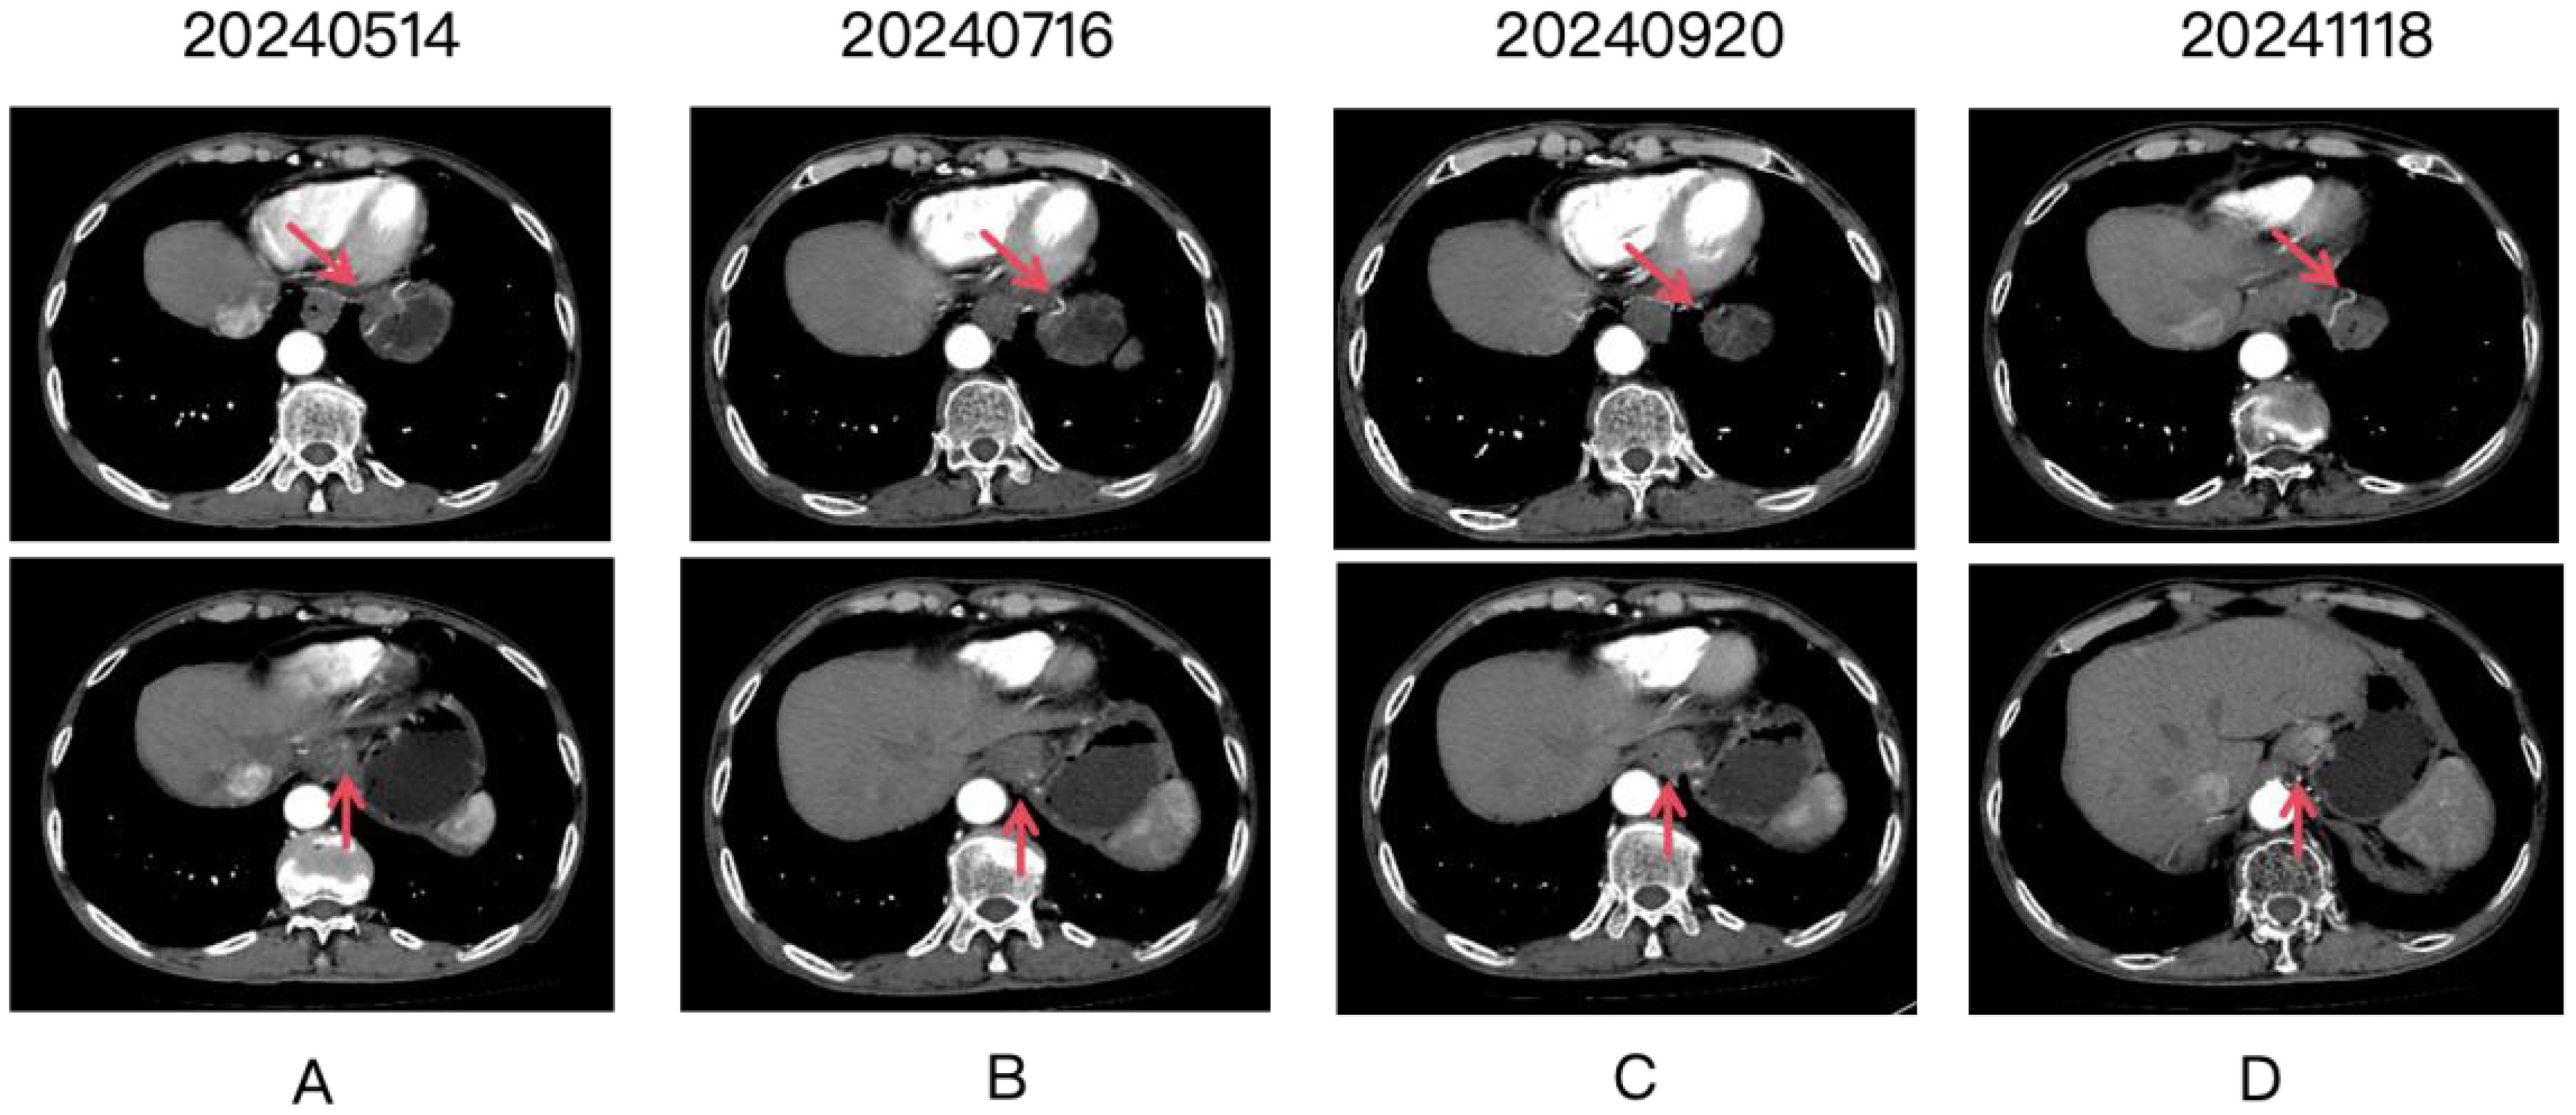

Four panels labeled A to D show CT scan images over time, with dates 20240514, 20240716, 20240920, and 20241118. Each panel contains two images. Red arrows point to a specific area, likely indicating a focus of medical interest.

Figure 1. Four panels labeled (A-D) show CT scan images over time, with dates 20240514, 20240716, 20240920, and 20241118. Each panel contains two images. Red arrows point to the gastric lesion, which shows a partial response after treatment.

In February 2024, with progressive weight loss, fatigue, and anorexia. Endoscopic biopsy (February 28, 2024) revealed adenocarcinoma of the gastroesophageal junction/cardiac fundus. Subsequent pathological consultation at Tianjin Cancer Hospital (March 12, 2024; H2402290) confirmed poorly differentiated adenocarcinoma at this location. Immunohistochemistry (IHC) demonstrated: HER2 (1+); Mismatch repair proteins: MLH1 (+), MSH2 (+), MSH6 (+), PMS2 (+); Combined Positive Score (CPS) = 2. On March 13, 2024, the patient was evaluated at Tianjin Union Medical Center of Nankai University. PET-CT (Waterdrop Medical Diagnostics Center) revealed: Focal wall thickening at the gastroesophageal junction/gastric fundus and lesser curvature with intense radiopharmaceutical uptake, consistent with gastric carcinoma with perigastric fatty infiltration and lymph node involvement. A 1.2 × 1.0 cm nodule adjacent to the descending aorta in the right lower lung posterior basal segment showing intense radiopharmaceutical uptake, suggestive of metastatic disease. Molecular profiling (Putihe Biotech; March 18, 2024) identified: ERBB2 amplification (copy number: 1.98-fold) No detectable mutations in MLH1, MSH2, MSH6, or PMS2. Based on comprehensive imaging and pathological findings, the patient was diagnosed with stage IV gastric adenocarcinoma with pulmonary metastasis, with molecular confirmation of HER2 gene amplification. First-line therapy was initiated in May 2024 with the following regimen: Inetetamab (300 mg IV, day 0), Tislelizumab (200 mg IV, day 0), Oxaliplatin (150 mg IV, day 1), Capecitabine (1.5 g twice daily, days 1-14). The patient completed 6 cycles of this combination therapy, with follow-up imaging demonstrating a partial response (Figure 1). Assessment of treatment safety revealed an absence of severe (Grade 3-4) toxicities. The only treatment-emergent adverse events were mild (Grade 1) allergic reactions, including transient rash, which resolved without intervention. Subsequently, maintenance therapy with inotuzumab ozogamicin plus tislelizumab was administered for 4 additional cycles. As of the last follow-up in February 2025, the patient remained progression-free, achieving a progression-free survival (PFS) of 12 months.